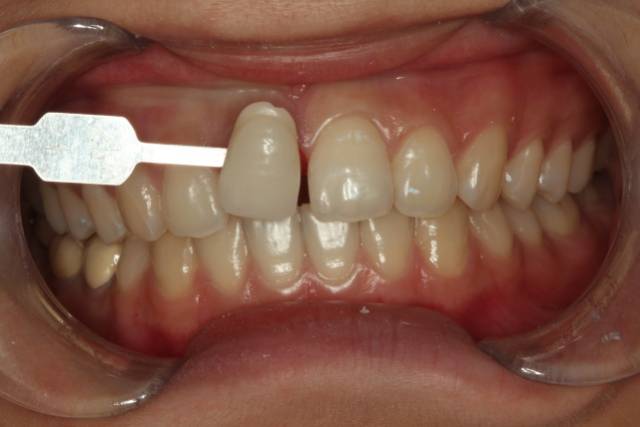

在口腔摄影里,因为拍摄环境的不同,所以需要黑板来增加摄影的成功率。黑色的物体可以吸收多余的干扰光,不仅能使主体颜色更加鲜明正确,还能与主体形成强烈的对比关系。

干货集结:

快门 1/125 、 光圈 F25 、 ISO 100

拍摄主体面向光源,不可多反光

比色板与牙齿保持于同一水平线